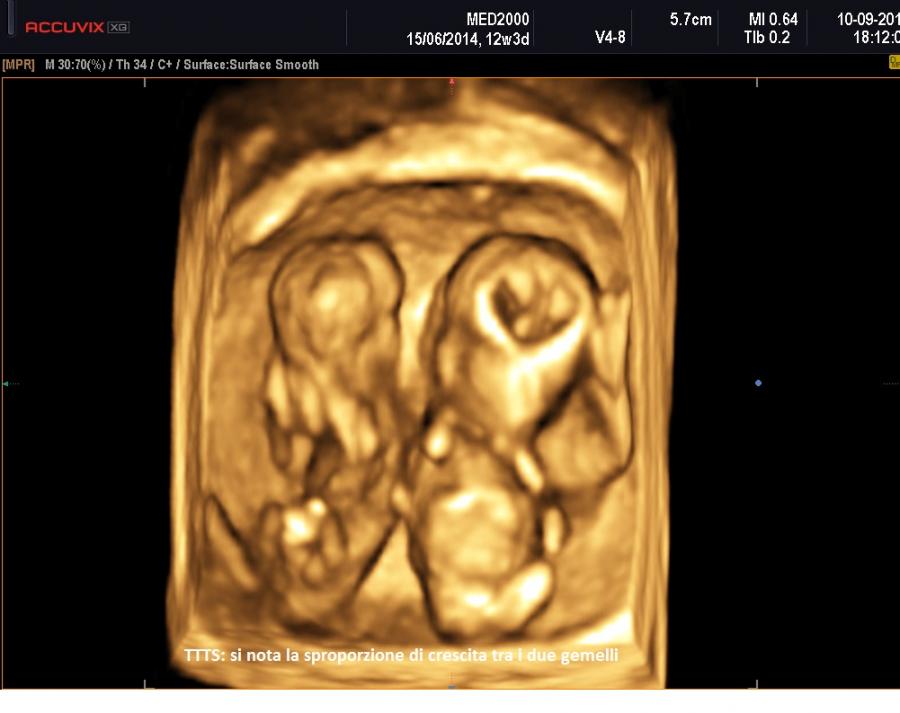

La diagnosi di sindrome da trasfusione feto-fetale è ecografica.

Prerequisiti essenziali per il sospetto diagnostico di TTTS sono:

A 11-14 settimane si sospetta una TTTS quando: